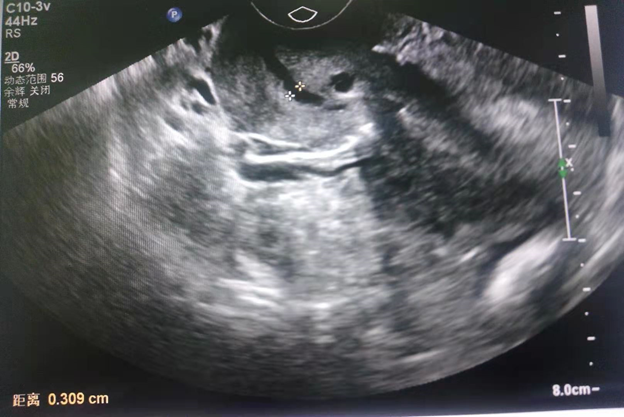

Chinese female 33 years old, G1P0, 23weeks 6days gestation age by scan, referred from a local hospital due to cervical insufficiency with cervical length of 0.309cm discovered during routine antenatal visit. (Figure 1) She presented to our hospital with complaint of lower abdominal pain which started 5 hours prior to presentation. She denied any history of vaginal bleeding, vaginal draining or discharge. Patient also denied any history of fever, headache, dizziness, cough or diarrhea. Married, other history was not significant for any risk of cervical incompetence. On physical examination, significant findings were noted on vaginal and speculum examination with open cervix of 5cm and unruptured membranes bulging through the cervical os (Figure 2).  An impression of inevitable abortion secondary to cervical insufficiency was made. Plan of emergency transvaginal cerclage placement, tocolysis/fetal protection with magnesium sulphate, oral progesterone, IV fluids for hydration, antibiotics for infection prevention and patient counselling was initiated within 1 hour after admission. The Shirodkar procedure was successfully performed without any complications after reducing the amniotic sac membranes back into the uterus (Figure 3).

Figure 1 Showing the short and opened cervix, (asterisks).